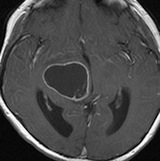

放射線治療後7週目

フレア画像です。腫瘍サイズが増大しています。もともと腫瘍周辺浮腫はなかったのですが大脳基底核と視床に浮腫が出現しています。スード・プログレッションの始まりです。

放射線治療後9週目

フレア画像です。たった2週間で脳浮腫が高度の脳浮腫となっています。失語症と右片麻痺と認知機能低下が生じました。ステロイド剤とグリセリンの点滴を行いました。